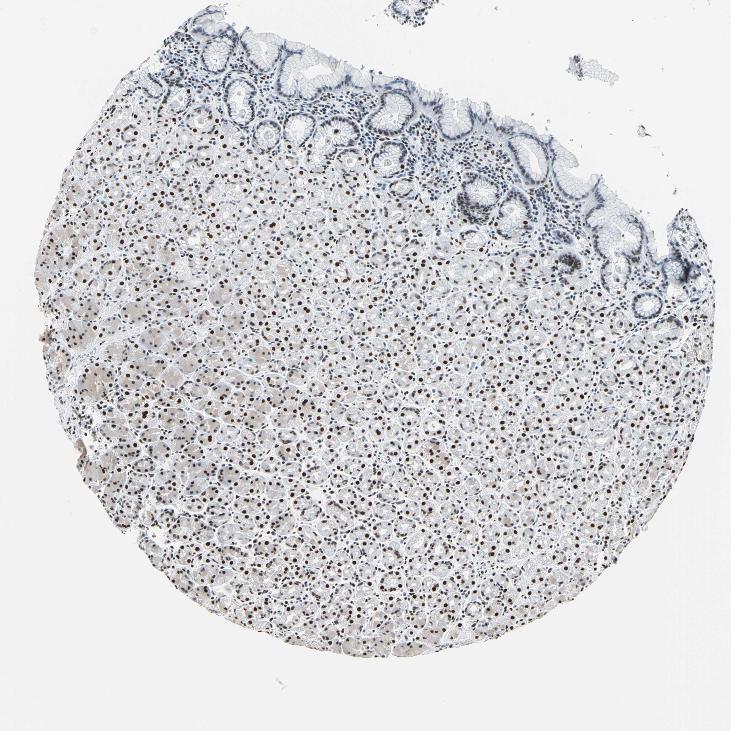

TISSUE PRIMARY DATA STOMACH Show tissue menu

STOMACH 1 - Antibody stainingi

Antibody staining in the annotated cell types in the current human tissue is reported as not detected, low, medium, or high, based on conventional immunohistochemistry profiling in selected tissues. This score is based on the combination of the staining intensity and fraction of stained cells.

Each image is clickable and will lead to virtual microscopy that enables deeper exploration of all samples and also displays staining intensity scores, fraction scores and subcellular localization as well as patient and tissue information for each sample.

Antibody HPA011727Antibody CAB005054

Glandular cells HighHigh